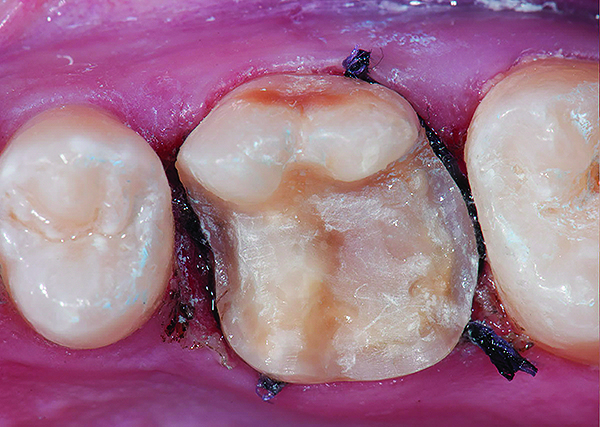

Fig 9. Preoperative view (Fig 9), preparation with composite block-out restoration (Fig 10), and final cementation of CL-IIb material (Fig 11) (final ceramic contour and stain by Steve Lee, CDT, MDC).

Fig 10. Preoperative view (Fig 9), preparation with composite block-out restoration (Fig 10), and final cementation of CL-IIb material (Fig 11) (final ceramic contour and stain by Steve Lee, CDT, MDC).

Figure 10

Fig 11. Preoperative view (Fig 9), preparation with composite block-out restoration (Fig 10), and final cementation of CL-IIb material (Fig 11) (final ceramic contour and stain by Steve Lee, CDT, MDC).

Figure 11